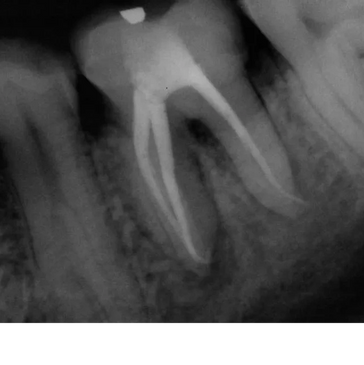

Root Canals have a great success rate . Studies Show their success rate is between 85-97 %. A properly treated and restored tooth can last a life time. Our goal is to provide you with the best and most affordable treatment. You can get a root canal and same day zirconia crown for around $1600.00 . The treatment is normally completed

Root Canals have a great success rate . Studies Show their success rate is between 85-97 %. A properly treated and restored tooth can last a life time. Our goal is to provide you with the best and most affordable treatment. You can get a root canal and same day zirconia crown for around $1600.00 . The treatment is normally completed in 1-2 appointments. It is the treatment of choice for most of our patients.